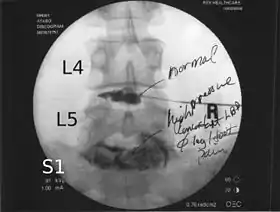

Lumbar provocative discography showing a degenerated disc, L5-S1 with normal disc L4-L5

Spinal MRI is the imaging of choice to investigate the spine and intervertebral discs.[1] Meanwhile, lumbar discography is used to demonstrate degeneration and herniation of lumbar intervertebral discs by injecting a dye into the nucleus pulposus of the discs. The procedure is also used to reproduce pain back pain for those who have such symptoms. Lumbar discography is also used to access the response of a subject to anaesthetic injection. Other uses include suspected discogenic pain without radicular sign (pain travelling to lower limbs along a dermatome) and confirmation of normal intervertebral discs above and below a site before spinal fusion.[1] However, evidence supporting the usefulness of lumbar discography in recognizing intervertebral disc problems is limited.[1] There is no role for cervical or thoracic discography in diagnosing disc pathologies at the cervical or thoracic regions.[1][2]

Non-ionic contrast media such as iopamidol and iohexol are used.[1] Needles are inserted through the back into the disc near the suspect area, guided by fluoroscopic imaging. Fluid is then injected to pressurize the disc, and any pain responses are recorded.